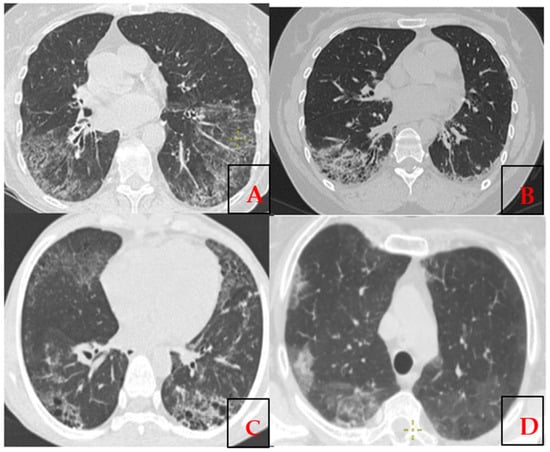

3.4. Immunogenetic Profiling of Kazakh Patients with SSc-ILD

3.5. Autoantibodies and Their Association in the Development of SSc-ILD

| HRCT | High-resolution computed tomography |